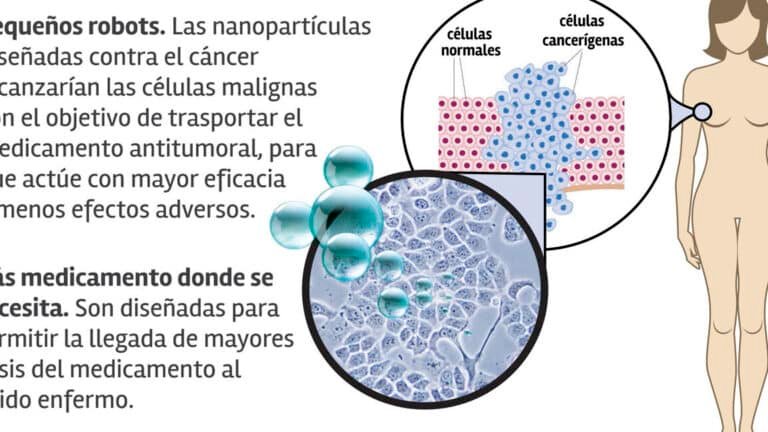

Los representan una innovación clave en el desarrollo de medicamentos más eficaces. Muchos compuestos terapéuticos presentan baja...

se ha convertido en un tema crítico en el campo de la nanotecnología y la medicina. Estas...